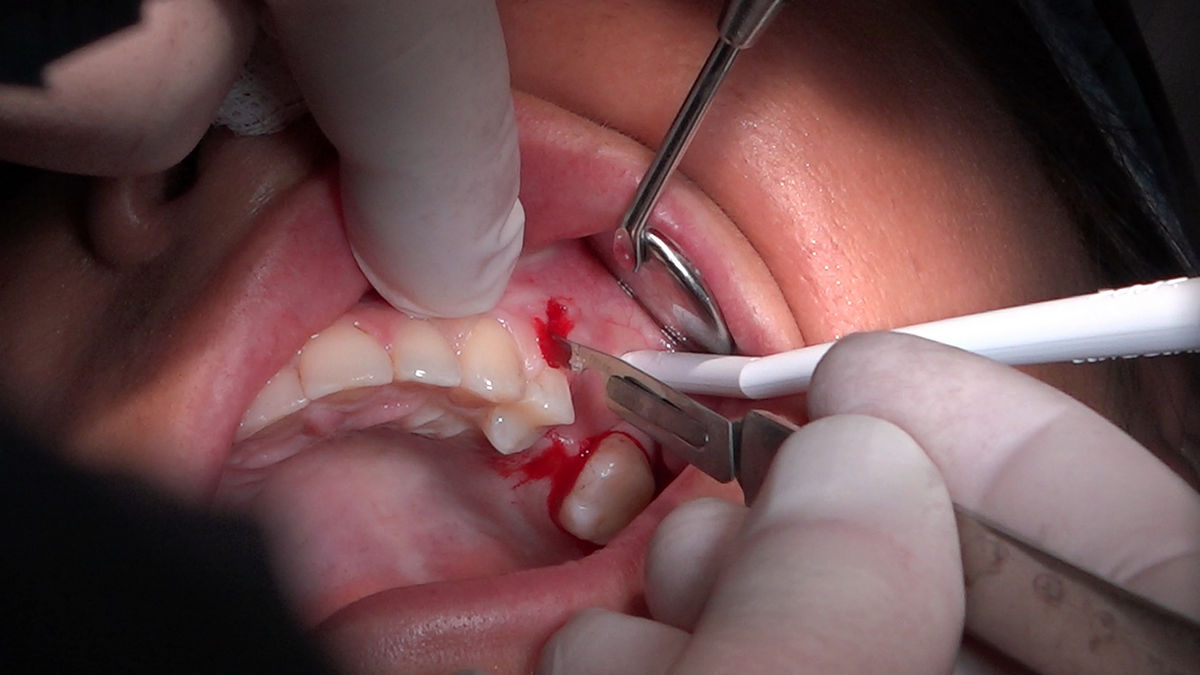

Chirurgia implantologiczna to temat wiodący 5 Sesji X Sezonu Practiculum Implantologii, która się odbyła 23-24 października 2020 roku. Bierze w nim udział 16 adeptów implantologii stomatologicznej. Zabiegi z udziałem Pacjentów jak zwykle poprzedziło omówienie i planowanie, tym bardziej, że zgodnie z planem wykonana została implantacja z wykorzystaniem szablonu chirurgicznego, który przygotowało laboratorium dentystyczne Wiligała Lab. Kursanci wykonywali szereg zabiegów implantologicznych i chirurgicznych oraz regeneracyjnych z zastosowaniem PRF, w tym sinus lift. Przeprowadzali je pod kierunkiem Lidera Umiejętności Implantologicznych dr n.med. Violetty Szycik, która wysoko oceniła wykonanie zabiegów.